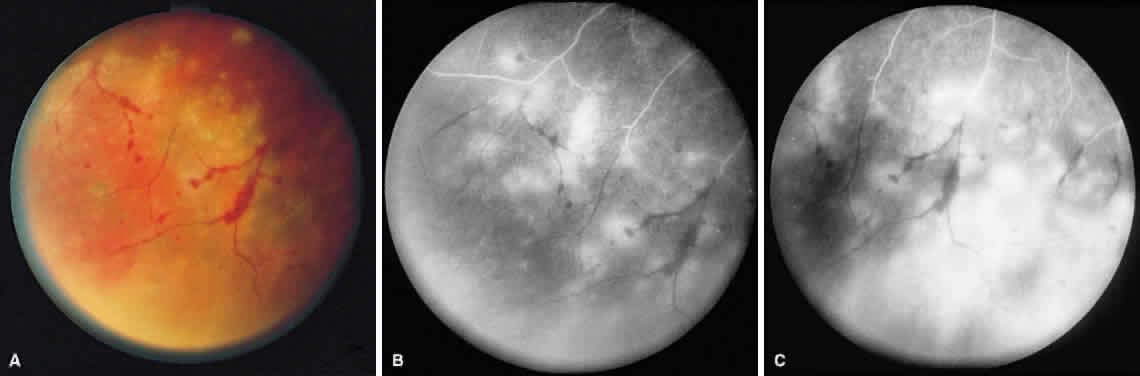

ARN is characterized by a retinal vasculitis affecting both the arteries and veins in the fundus, which is manifested by sheathing of the larger vessels (Fig. 2).7–10,16 Initially, patchy areas of peripheral retinal whitening (“thumbprint lesions”) representing full-thickness retinal necrosis are present or develop shortly after the vasculitis (Fig. 3). During a course that may span days or weeks, these patches coalesce into geographic areas (Fig. 4A). The entire peripheral retina (360 degrees) may be involved, or, more commonly, there are several noncontiguous patches of necrosis, each covering from a half to three clock hours (Figs. 5 and 6). The posterior segment lesions may not be detected without examination of the peripheral retina.

As the infection progresses, the leading edge of confluent retinal whitening advances toward the posterior pole (Fig. 7A). The retinitis may not progress posteriorly to the vascular arcades, sparing the macula and central vision. It is hypothesized that the retinal necrosis in ARN results from the combined effect of intracellular viral replication with subsequent cell death and vascular occlusion secondary to acute vasculitis. In some patients, the retinal vasculitic component may be much more prominent than the retinal necrosis.7 Optic disc swelling, either hyperemic or pallid, is a common feature of the ARN syndrome.1 Perivascular hemorrhages may be present (Fig. 8); however, widespread areas of retinal hemorrhage are atypical. Retinal vascular occlusion, often involving the arteries, can occur at any point during the clinical course. Without treatment, the inflammatory component of ARN typically burns out in 6 to 12 weeks, leaving behind a thin atrophic retina with associated pigmentary changes.10

Intravenous fluorescein angiography may be helpful in delineating the extent of infection and elucidating the cause of central visual loss. In the early frames, choroidal perfusion defects may be seen; these defects are caused by areas of focal choroidal inflammatory cell accumulation and overlying retinal pigment epithelial damage (Fig. 16). Such choroidal perfusion defects may occur away from zones of active necrosis.42 Acute obstruction of the central retinal artery or any of its branches may be present. Peripheral views in the areas of active retinitis commonly show little or no intravascular fluorescein in the retinal arteries and veins. Often an abrupt “cut-off” of the intravascular fluorescein may be apparent at the edges of the retinal inflammation (see Fig. 4B and C). Areas of active retinitis show blockage of the underlying choroidal fluorescein pattern (see Fig. 7B). Recirculation phase views may reveal macular leakage, optic disc, and retinal vasculature staining.